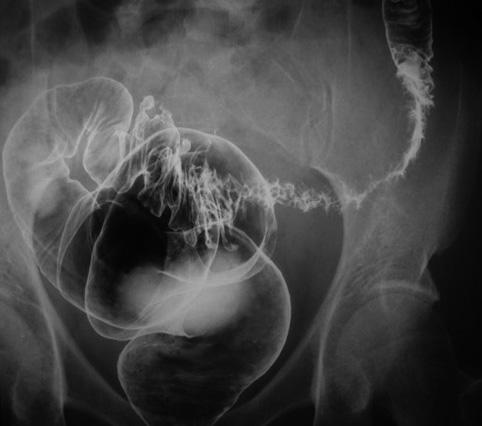

S상 결장의 다발성 게실과 게실주위종양

게실/게실염 및 게실주위농양

대장/S상

X-P